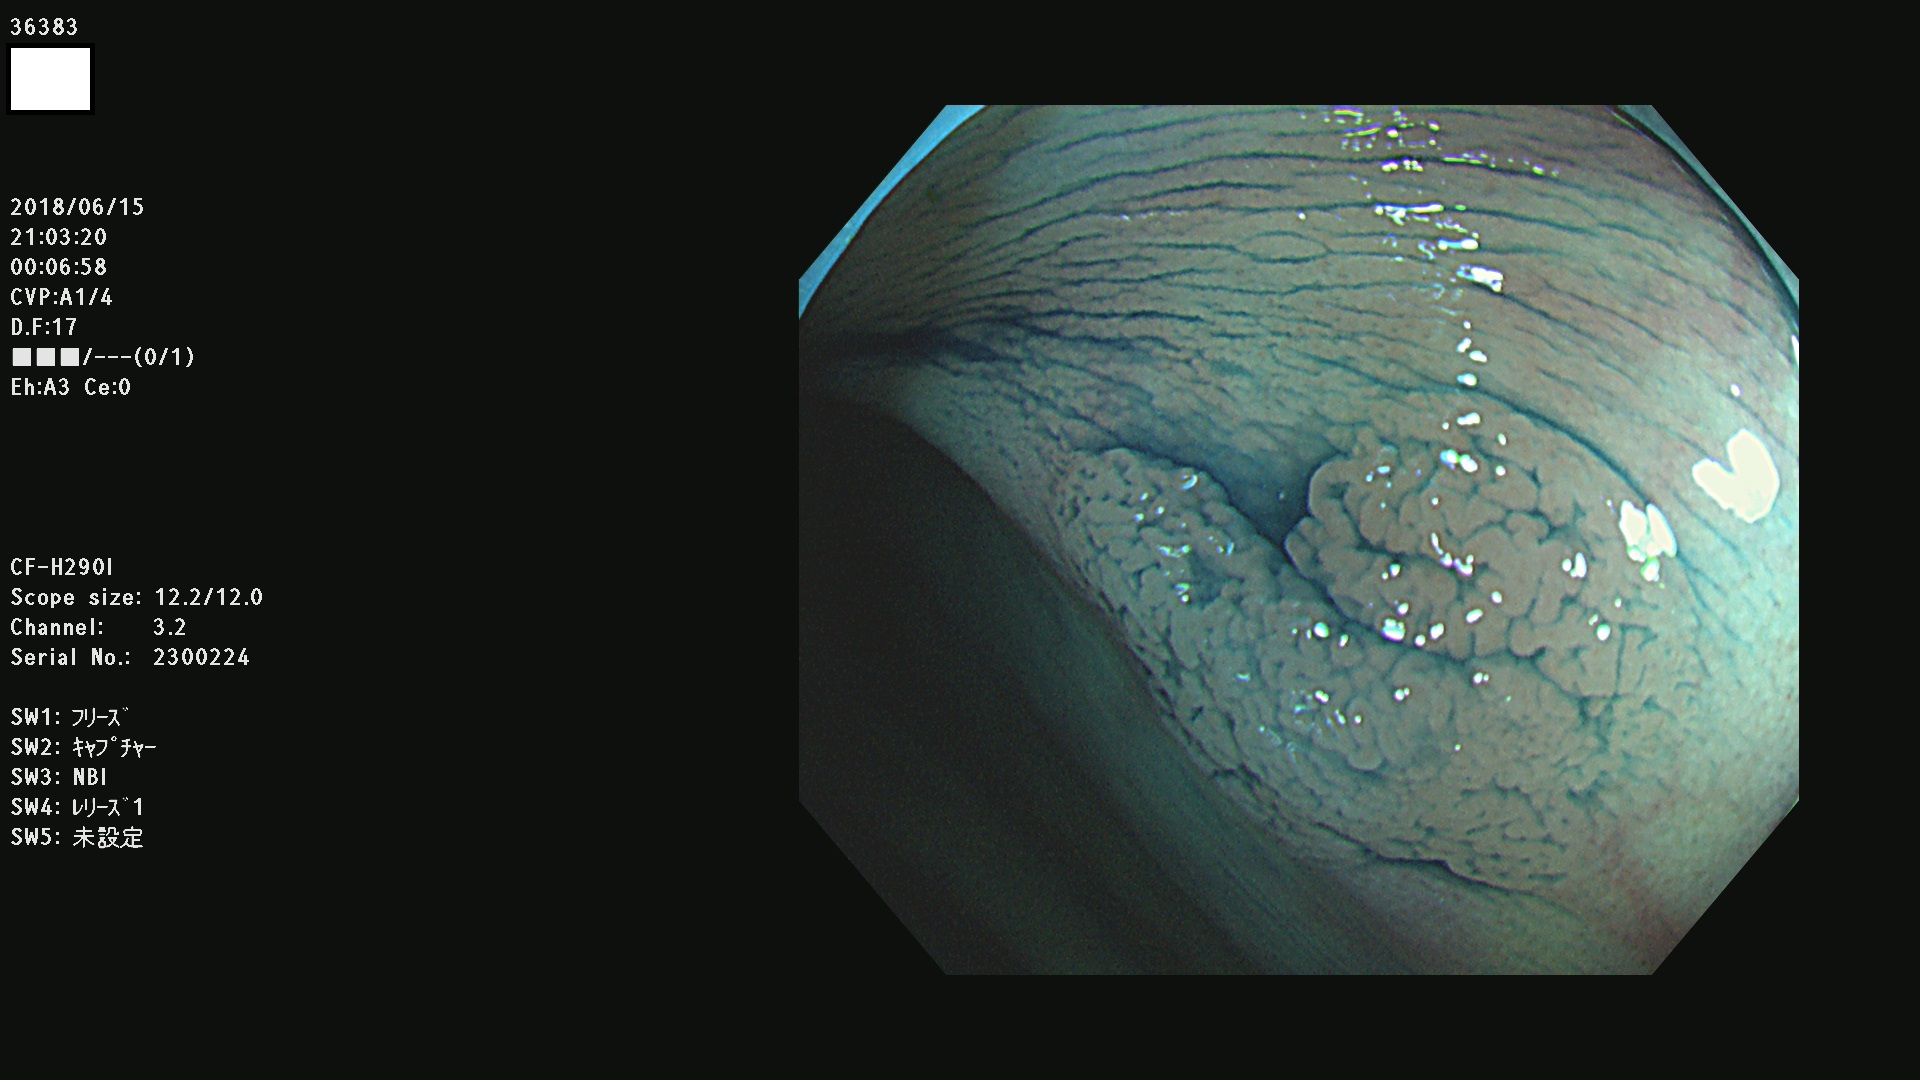

腺腫発見率 68 % (カルテ番号 36300〜36399の100名の方の検査結果で集計)大腸癌検診最新情報

以下のカルテ番号の方に腺腫(Adenoma,Group3〜5)が見つかりました(集計法)

36300 36302 36305 36306 36307 36308 36310 36311 36312 36313 36314 36315 36316 36318 36321 36322 36324 36325 36326 36327 36330 36332 36333 36334 36335(SSAPのみ) 36337 36338 36339(SSAPのみ) 36340 36341 36342(SSAPのみ) 36343 36344 36346 36348 36349 36351 36353 36354 36355(SSAPのみ) 36356 36357 36358 36359 36364 36365 36366 36367 36370 36374 36376 36379 36381 36382 36383 36384 36385 36387 36388 36389 36390 36392 36393 36395 36396 36398 36399

発見困難で危険性の高い平坦型病変(上記100名より抽出) ![]()